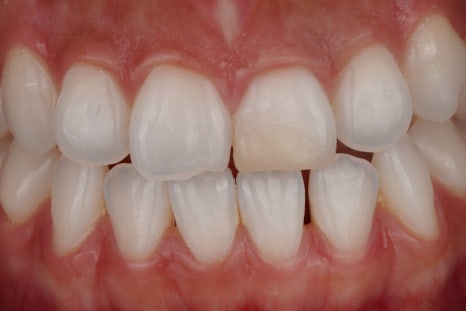

3주 뒤

치아 상태에 따라 한 번으로 끝나는 경우도 있지만 보통은 몇 차례 반복하면서 주변 인접치와 자연스럽게 어울리는 색을 맞춰 가고 있어요.

산소가 빠지려면 충분한 시간을 기다리는 것이 중요하거든요.

완료 후

한 2주 정도 기다리면 이렇게 건강한 자연치와 같은 모습으로 바뀌게 된답니다^^

크라운 없이 치료 완료